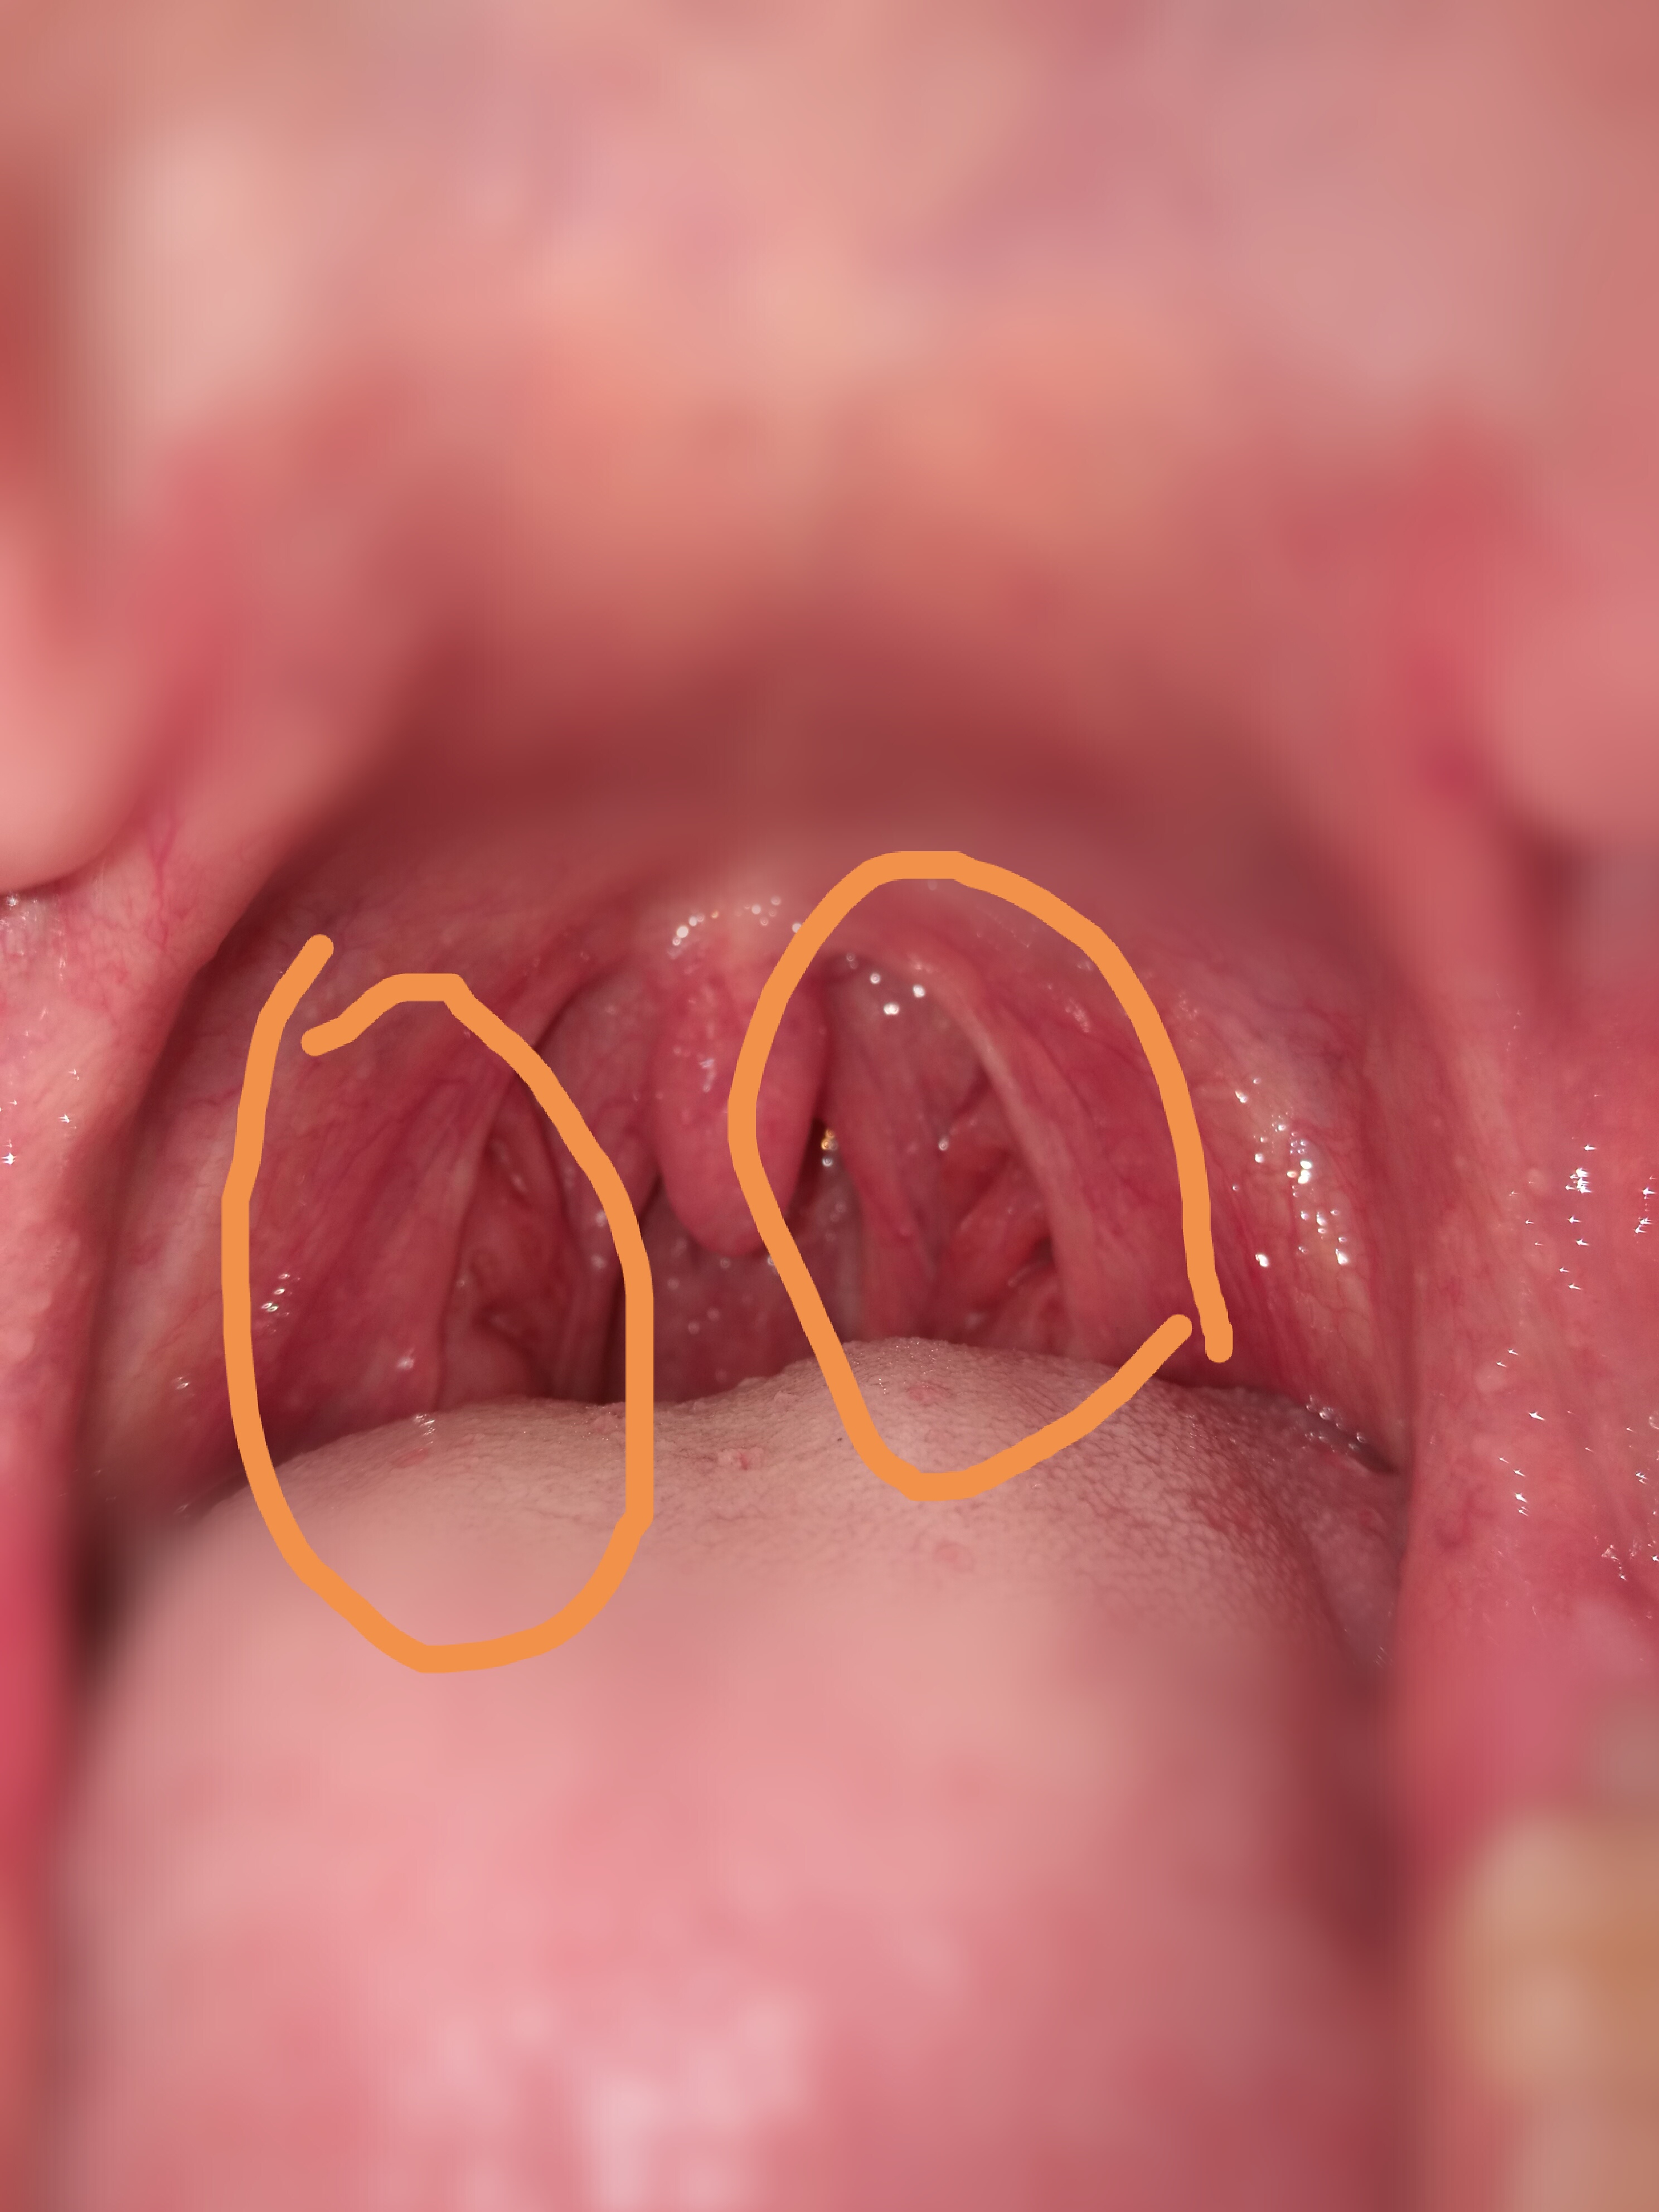

Was ist evolution?. Rmjm evolution tower moskau. Krebs tumor arzt rachen tumore antworten anonym gutefrage

krammer Rmjm evolution tower moskau. Muss ich zum arzt, krebs? (gesundheit, tumor, rachen). Ein blick über wälzlager hinaus: zahnräder

Was ist evolution?. Books about evolution. Muss ich zum arzt, krebs? (gesundheit, tumor, rachen)

Muss Ich Zum Arzt, Krebs? (Gesundheit, Tumor, Rachen)

krebs tumor arzt rachen tumore antworten anonym gutefrage Fett an der hüfte wegbekommen, aber wie? (abnehmen, figur). Was ist evolution ?. Rmjm emporis moskau moscu moscou floornature twisting skyscrapers archinect moscú igor

uncyclopedia evo3 Krebs tumor arzt rachen tumore antworten anonym gutefrage. Evolution definition ist. Die evolution / the evolution

Krebs tumor arzt rachen tumore antworten anonym gutefrage. Was ist evolution ?. Rmjm evolution tower moskau